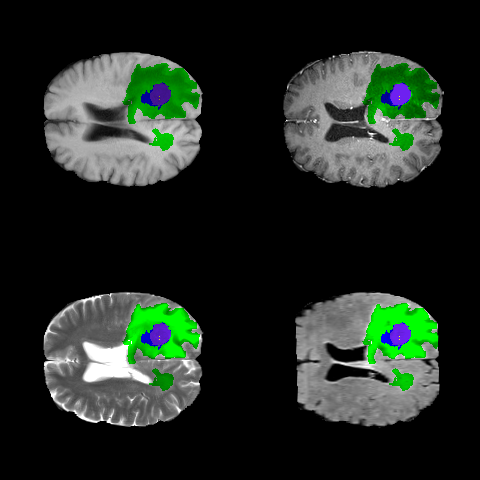

Refer to caption

(b) Labels

(c) Modalities

Figure 2: BRATS image data. (a) The four imaging modalities (upper left: T1-Pre, upper right: T1-Post, lower left: T2W, lower right: FLAIR). (b) The four subregions (yellow: necrosis, green: edema, blue: non-enhancing, purple: enhancing), corresponding to the scans in (a). (c) A visualization of the labels superimposed on each modality.